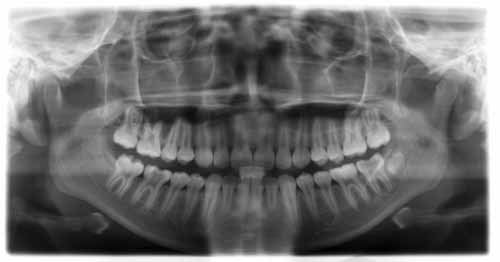

临床诊断:经过数字化全景机的拍片检查,顾客属于牙性地包天,且存在上牙拥挤错位,侧貌突,下颌前倾,X片显示根尖无异常。由于顾客的职业特殊性,可选择天使隐形正畸,在旁人无法擦觉的情况下完成整个矫正过程,顾客对此方案表示愿意接受,并十分期待矫正后的效果。

全景机正位片